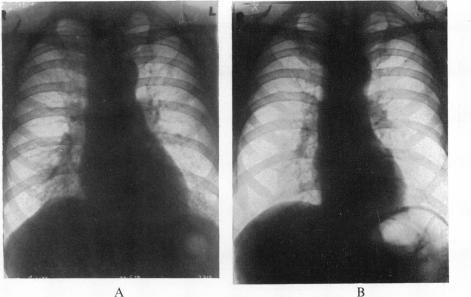

CARDIOVASCULAR DISTURBANCES CAUSED BY DEFICIENCY OF VITAMIN B(1).

Br Heart J. 1940 Oct;2(4):231-40. doi: 10.1136/hrt.2.4.231.